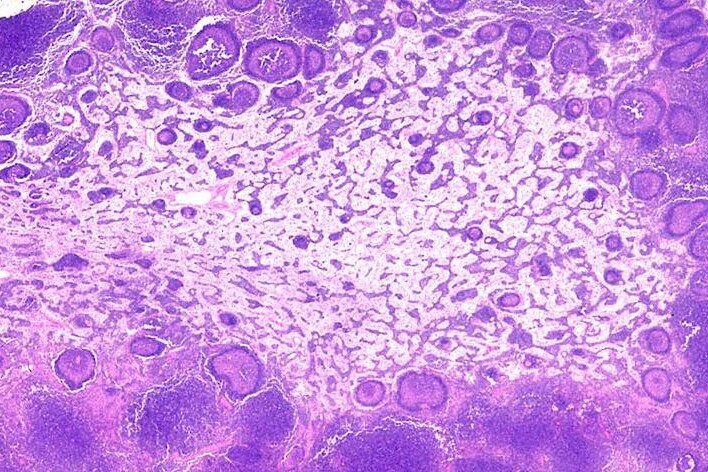

Nejspolehlivější metodou, jak zjistit přesně příčinu zvětšení uzlin, je biopsie. Chirurg vyjme v místním nebo i v celkovém znecitlivění celou zvětšenou uzlinu, kterou patolog mikroskopicky vyšetří. Hodgkinovu nemoc se tak podaří spolehlivě rozpoznat.